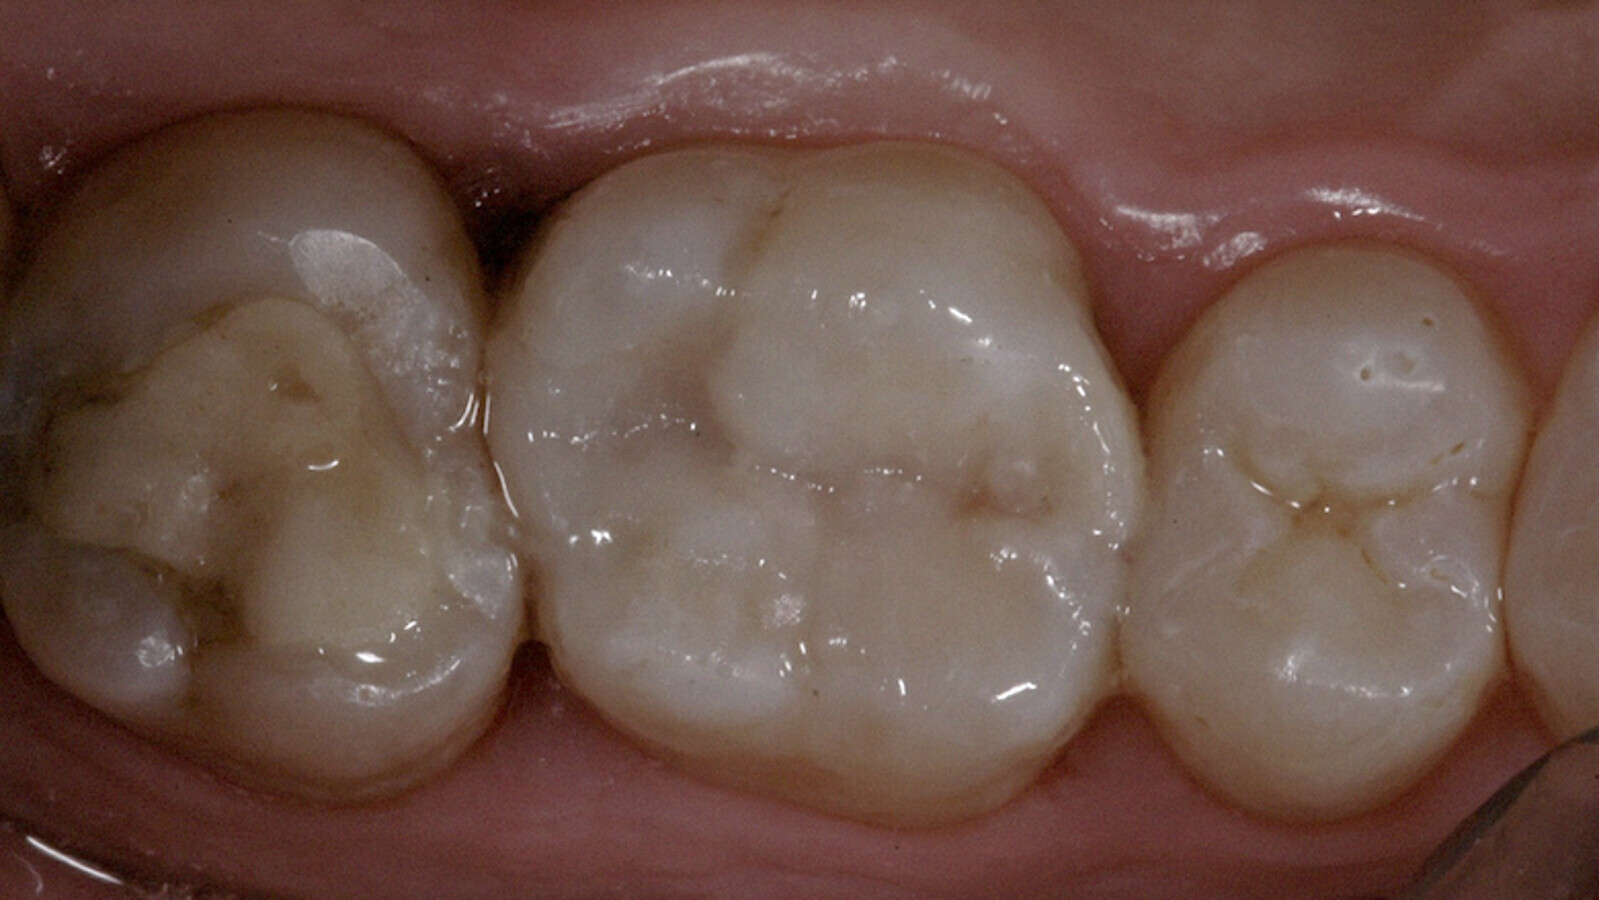

Uno de los desafíos actuales es poder realizar una adecuada preparación dentaria “sin tocar los dientes vecinos”, y luego restaurar la forma y función de la pieza, logrando un punto de contacto ajustado para evitar el atrapamiento de alimento con el consecuente problema periodontal y caries recurrente. Según un estudio, el odontólogo general lastima el diente vecino en un 100% de las intervenciones de clase II (6). Es por esta razón que la elección de un sistema de matrices que permitan proteger el diente vecino durante la preparación resulta de real importancia. Este sistema debe permitir también que la curvatura, forma y volumen de la caja proximal logre una correcta anatomía y punto de contacto (Fotos 1,2).

Foto 2. Restauración de clase II con pieza vecina lastimada en la preparación y punto de contacto incorrecto (se percibe bien el punto de contacto incorrecto y el daño a la pieza vecina).